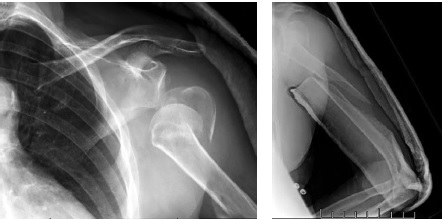

A 73-year-old patient applied to the European Clinic of Sports Traumatology and Orthopaedics (Mocow) 4 days after the injury resulting from a fall on the left upper limb. An X-ray examination was performed on admission, a multi-fragment fracture of the proximal and middle thirds of the humerus was diagnosed (Fig. 1). Additionally, signs of neuropathy of the left radial nerve and secondary anemia due to blood loss (hemoglobin of 110.0 g/L, erythrocytes of 3.53×1012/L, and hematocrit of 32.10%) were detected.

Fig. 1. X-rays of the left shoulder at admission: multi-comminuted fracture of the proximal and middle thirds of the humerus, dislocation of the humeral head